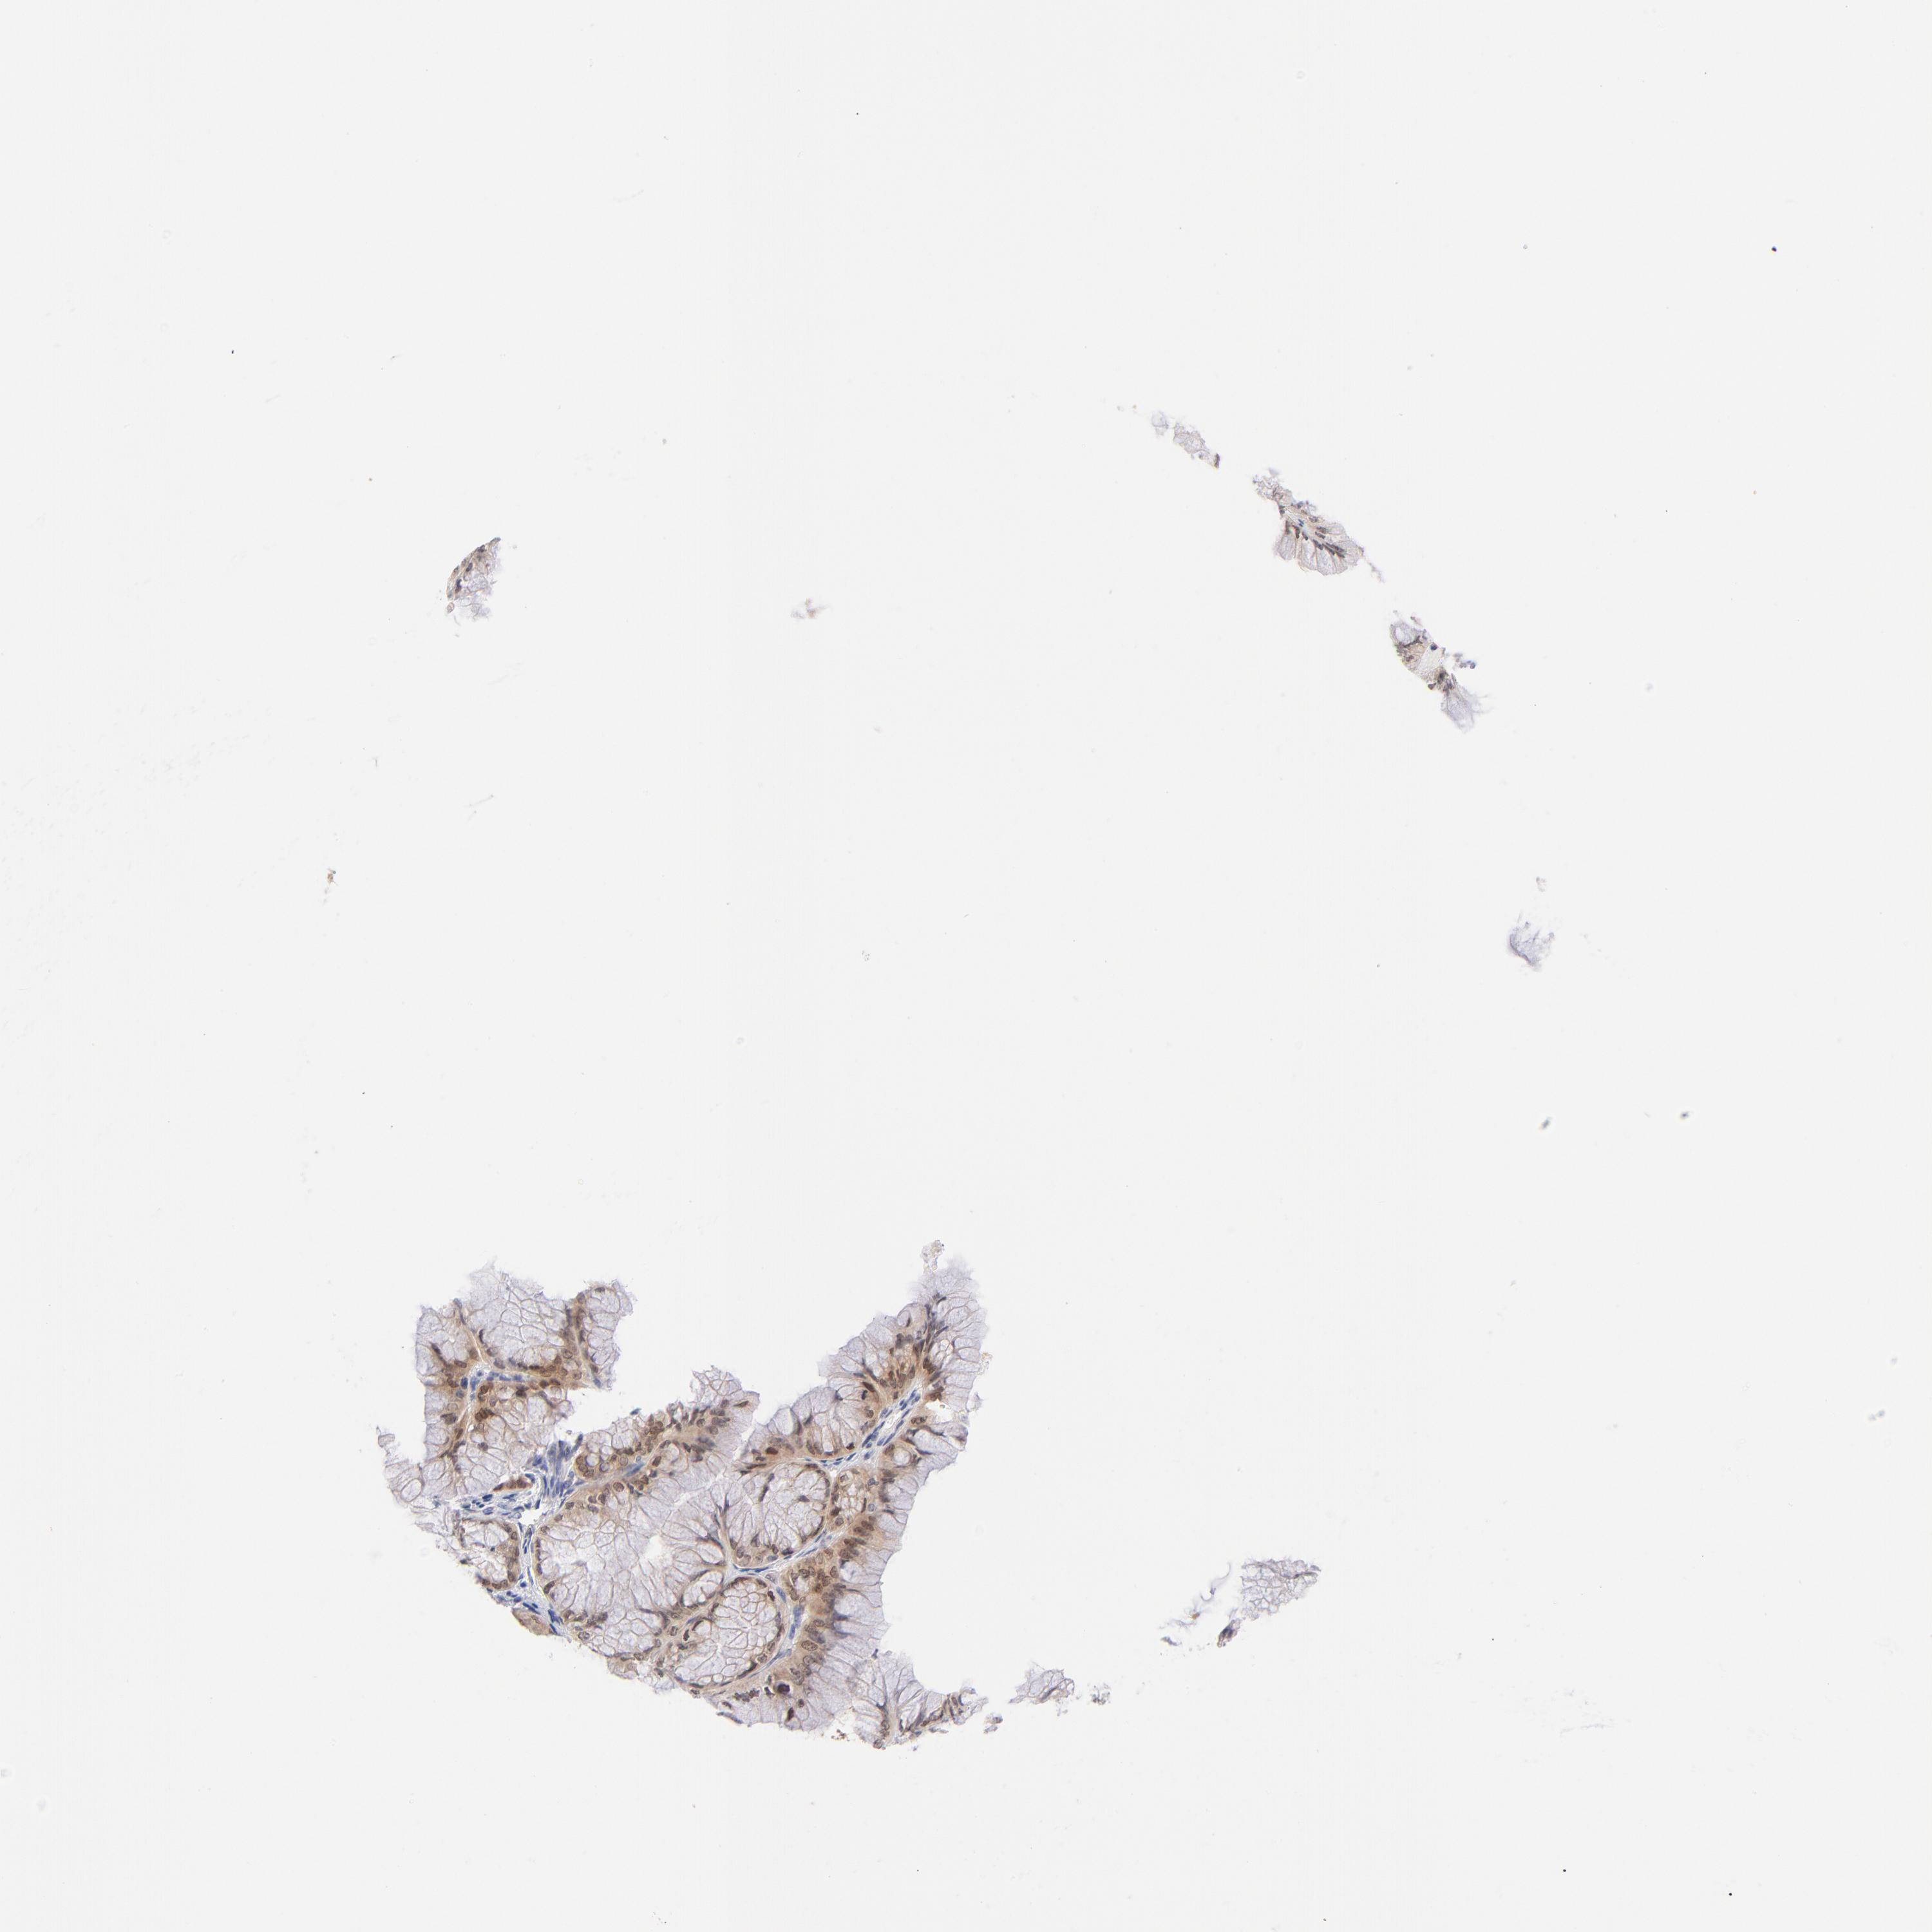

OVARIAN CANCER - Protein expressioni

A mouse-over function shows sample information and annotation data. Click on an image to view it in a full screen mode. Samples can be filtered based on level of antibody staining by selecting one or several of the following categories: high, medium, low and not detected. The assay and annotation is described here.

Note that samples used for immunohistochemistry by the Human Protein Atlas do not correspond to samples in the TCGA dataset.

Antibody stainingi

Antibody staining in the annotated cell types in the current human tissue is reported as not detected, low, medium, or high, based on conventional immunohistochemistry profiling in selected tissues. This score is based on the combination of the staining intensity and fraction of stained cells.

Each image is clickable and will lead to virtual microscopy that enables deeper exploration of all samples and also displays staining intensity scores, fraction scores and subcellular localization as well as patient and tissue information for each sample.

Antibody HPA011337

Antibody HPA024303

Antibody CAB003775

Carcinoma, endometroid

Cystadenocarcinoma, mucinous, NOS